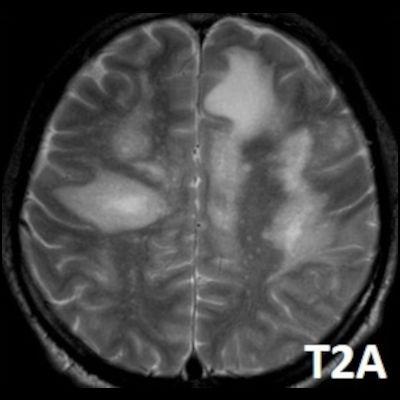

- Bilateral asimetrik subkortikal ve derin beyaz cevherde T1 ağırlıklı görüntülerde belirgin hipointens (oklar), T2A görüntülerde hiperintens (oklar), gri cevhere bakan kesimi düzgün (oklar), DAG’de hiperintens (ok) lezyonlar izlendi. Lezyonlarda T2/FLAIR uyumsuzluğu vardı (ok). Serebellar beyaz cevherde dentat nukleusu koruyan hilal işareti görüldü (ok başı). SWI sekansta sol motor kortekste hipointens kronik glioinflamatuar reaksiyon ile uyumlu sinyal değişikliği izlendi (ok başı).

- Çoğunlukla subkortikal beyaz cevherde ve U fiberlerde, asimetrik, genelde kitle etkisi yapmayan ve kontrastlanmayan demiyelinizan lezyonlar görülür. Korteks ve derin gri cevher tutulumu daha nadirdir.

- PML lezyonları, T1A görüntülerde belirgin hipointenstir. Gri cevhere bakan yüzleri keskin olup T2/FLAIR uyumsuzluğu önemli özelliğidir.